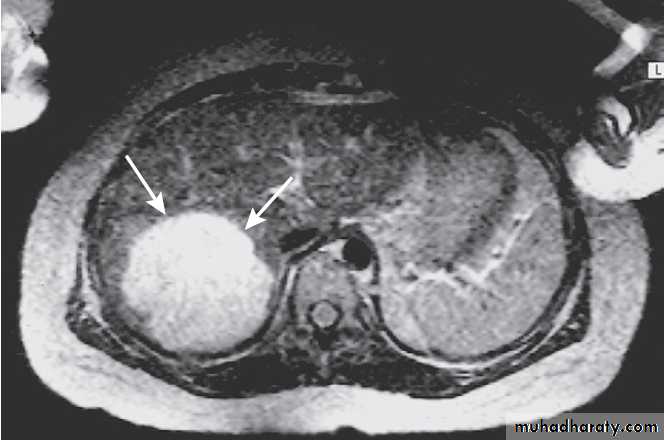

Hydatid cyst of the liver on CT (arrows).